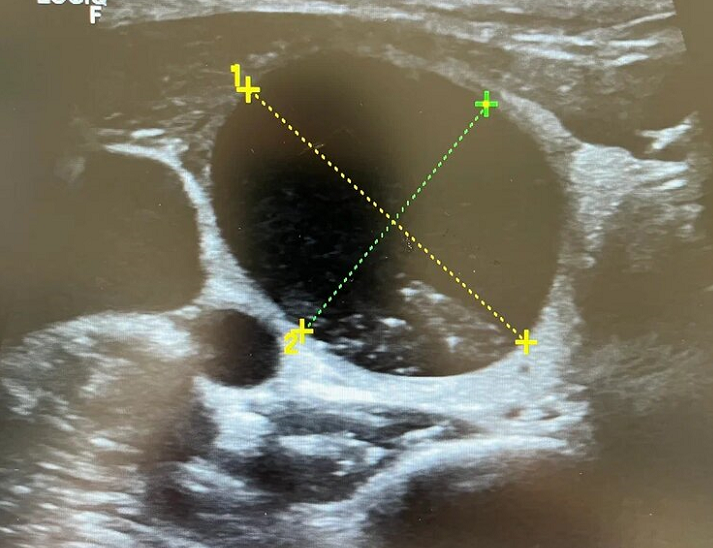

Ультразвуковое исследование щитовидной железы проводится с целью оценки ее тканевой структуры, измерения размеров и выявления очаговых образований (кист и узлов). Это достаточно простой и дешевый метод, не требующий особой подготовки, не отнимающий много времени. За счет поверхностного расположения органа можно использовать высокочастотный датчик, дающий высокое разрешение картинки, на котором можно рассмотреть образования от 1-2 мм в диаметре. УЗИ щитовидной железы одно из простых во всей ультразвуковой диагностике. Иногда возникают сложности в самом описании узлов и присвоении им градации по шкале TI-RADS. Самое важно, на что необходимо обращать внимания - это узлы. Они могут быть разного размера, иметь различную структуру, но самое страшное, что некоторые могут быть злокачественными. Обнадеживает то, что все это хорошо видно на ранних стадиях. При больших размерах узлов или высоких градациях по TI-RADS показана пунктирная биопсия. С помощью биопсии уже можно окончательно установ

Ультразвуковое исследование щитовидной железы проводится с целью оценки ее тканевой структуры, измерения размеров и выявления очаговых образований (кист и узлов).

Это достаточно простой и дешевый метод, не требующий особой подготовки, не отнимающий много времени. За счет поверхностного расположения органа можно использовать высокочастотный датчик, дающий высокое разрешение картинки, на котором можно рассмотреть образования от 1-2 мм в диаметре.

УЗИ щитовидной железы одно из простых во всей ультразвуковой диагностике. Иногда возникают сложности в самом описании узлов и присвоении им градации по шкале TI-RADS.

Самое важно, на что необходимо обращать внимания - это узлы. Они могут быть разного размера, иметь различную структуру, но самое страшное, что некоторые могут быть злокачественными.

Обнадеживает то, что все это хорошо видно на ранних стадиях. При больших размерах узлов или высоких градациях по TI-RADS показана пунктирная биопсия.

С помощью биопсии уже можно окончательно установить природу узла и определить его на злокачественные клетки.

Существует градация по шкале TI-RADS, которая складывается из характеристик очаговых образований. Чаще ключевым для показаний является размер узла. Но иногда и маленькие узелки могут быть оценены более TI-RADS 4, что потребует гистологического изучения.

Основные критерии злокачественных узлов:

• Нечеткость и неровность контуров, бугристая граница

• Деформирование капсулы ЩЖ

• Вертикальная ориентация

• Динамический рост

• Сниженная эхогенность

• Активный кровоток внутри узла

• Большой размер

Но все это оценивается комплексно по шкале TI-RADS.